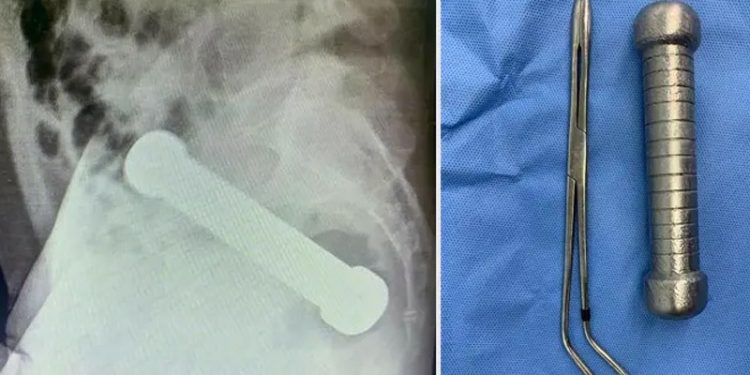

Doktorlar, yapılan röntgen görüntülemenin ardından adamın makatında, “seks oyuncağı gibi görünen” bir dambıl bulduklarını açıkladı.

Adamın acil ameliyata alındığı aktarıldı. Cerrahlar için zor bir operasyon olan ameliyatta manuel çıkarma yöntemi kullanmak zorunda kalındı. Cerrah, koluyla adamın vücudundan dambılı çıkardı.